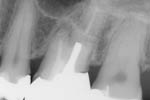

Ist die Revision nach Resektion machbar und erfolgreich? – ein Fallbericht

Autor(en): Göbbels M.

Fundstelle: ZWR – Das Deutsche Zahnärzteblatt 2015; 124 (7+8): 344–347

Die Revision eines zuvor wurzelspitzenresezierten Zahns bietet im Vergleich zu einer wiederholten Resektion entscheidende Vorteile. Durch den orthograden Zugang besteht die Möglichkeit der vollständigen Desinfektion des infizierten Wurzelkanalsystems. Parallel können durch Inspektion (IKD) mittels optischer Vergrößerung (Dentalmikroskop) Ursachen wie unbehandelte Wurzelkanäle, Isthmen, Stufen etc. erkannt und sicher therapiert werden, welche durch eine Wurzelspitzenresektion (WSR) nicht zu beeinflussen sind. Vor allem der Ausschluss von Frakturen, die nicht bis zum Neoapex reichen, ist für die Prognose des Zahns entscheidend.